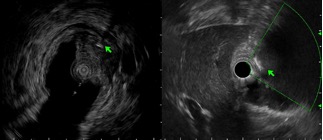

随后进行了超声内镜下的定位,黏膜下层及固有肌层分界不清,见一高回声条状带,提示异物已嵌入固有肌层突出腔外(图3)。

图3超声内镜:黏膜下层-固有肌层见条带状高回声异物(绿色箭头)